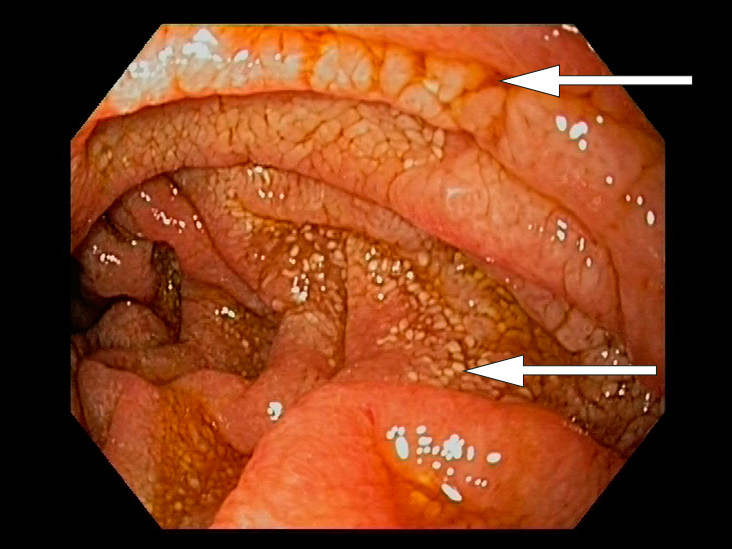

Konstellasjonen av migrerende leddsmerter og synovitter over flere år uten utvikling av radiologiske artrittforandringer, kombinert med intermitterende diaré og proteintapende enteropati gjorde at vi mistenkte Whipples sykdom, en sjelden infeksjonssykdom forårsaket av den grampositive bakterien Tropheryma whipplei. Pasienten ble henvist til gastroskopi og kapselendoskopi av tynntarm som viste betydelig inflammasjon med erosjoner, hemoragiske slimhinner og diffus lymfangiektasi (fig 2) (fig 3). Duodenalbiopsier viste breddeøkte totter og akkumulering av skummakrofager med periodisk syre-Schiff (PAS) diastasepositive granulære inklusjoner i cytoplasma (fig 4) (fig 5). Både de makroskopiske og histopatologiske funnene var godt forenlig med Whipples sykdom. PCR utført etter DNA-ekstraksjon fra parafininnstøpt tarmbiopsi var positiv for T. whipplei for to separate målgener (varmesjokkprotein og 16S rRNA). Sekvensering av 16S rDNA PCR-produktet bekreftet T. whipplei. Pasientens ikke-destruktive seronegative artritt, diaré, malabsorpsjon og utmattelse ble antatt å representere manifestasjoner av Whipples sykdom. Iskemiske slag og lungeembolier er beskrevet hos pasienter med Whipples sykdom, og sykdommen representerte en plausibel årsak til pasientens hittil uforklarlige trombosetendens (1),( 2).

Klassisk Whipples sykdom diagnostiseres på bakgrunn av øvre endoskopi, duodenalbiopsier og PCR-undersøkelse. Gastroskopi kan vise ødematøse slimhinner med erosjoner og lymfangiektasi. Lymfangiektasien skyldes akkumulering av makrofager i lymfekarene, med resulterende lymfestase. Allikevel er det viktig å være klar over at de fleste pasientene har makroskopisk normal tynntarmsslimhinne, så biopsier anbefales selv ved upåfallende gastroskopi (5). Multiple biopsier øker sensitiviteten (6). Kapselendoskopi av tynntarm kan brukes for å kartlegge sykdomsutbredelsen. Mikroskopering av duodenalbiopsi viser akkumulering av skummakrofager med PAS-positive intracellulære inklusjoner. Det PAS-diastase-positive materialet svarer til bakteriekapselen som inneholder mykopolysakkarider. Andre årsaker til PAS-positive makrofagansamlinger i tynntarm er blant annet mykobakterieinfeksjon, avleiringssykdommer og langerhanscelle-histiocytose. Disse differensialdiagnosene kan avkreftes med tilleggsundersøkelser.